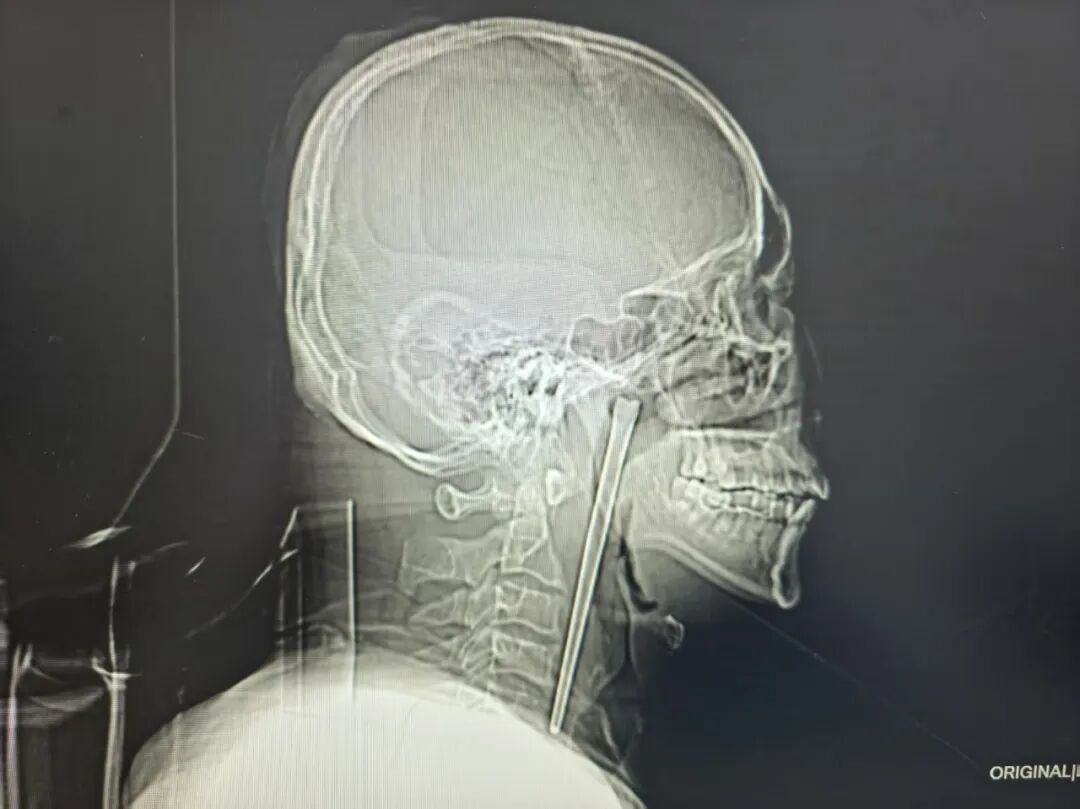

检查结果清晰显示,王先生右侧咽后壁上方软腭后侧有一根金属筷子嵌入其中,外露部分约3厘米。

万幸的是,经细致探查,异物邻近的咽部黏膜未出现明显破溃、出血及化脓情况,声带活动正常,喉腔结构也未受到压迫移位。

考虑到王先生8年前因顾虑颈部切开手术的创伤而放弃治疗的过往,医生为其定制经口腔取异物的微创手术方案,无需颈部开刀的治疗方式。最终将这根长达12厘米的不锈钢筷子完整取出。整个手术过程十分顺利,术中出血量极少,未出现任何手术并发症,让患者和家属悬着的心终于落地。